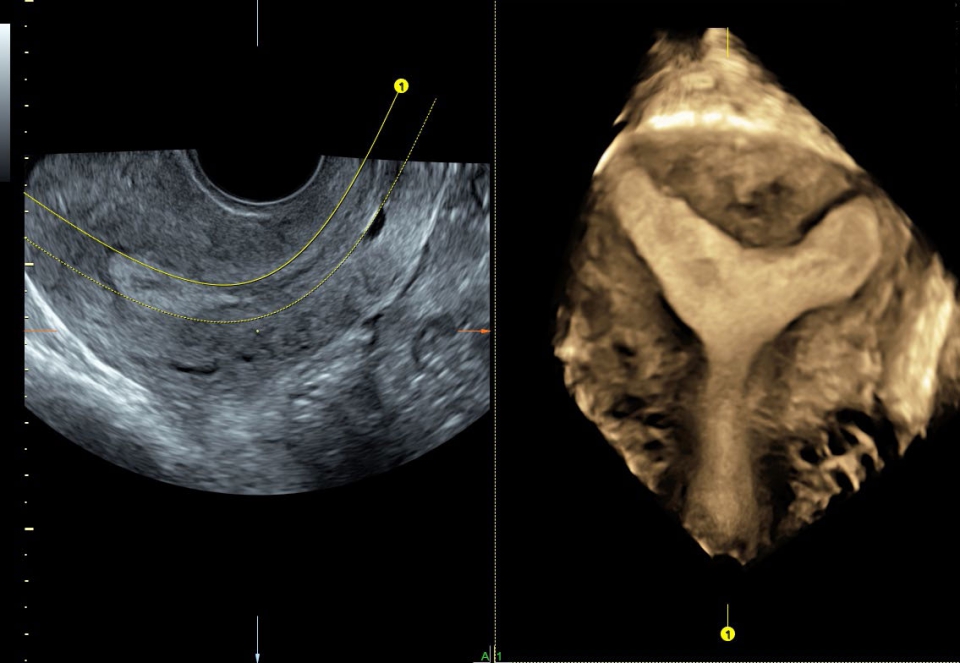

УЗИ аппарат Voluson S10 позволяет проводить обследования высочайшего уровня с максимальной точностью диагностики. Благодаря технологии Voluson Core Architecture достигнут высокий уровень качества изображений с возможностью последующей обработки и анализа даже после проведения скрининга. Технология HDlive делает изображения удивительно реалистичными и объемными.

• SonoRenderlive (Автоматическое объемное изображение): Эта функция упрощает получение объемного изображения путем автоматического выбора положения плоскости визуализации для 3D- и 4D-режимов. Это сокращает необходимость вручную настраивать параметры и упрощает процесс получения объемных изображений.

• SonoAVC (Автоматический расчет объема): Эта функция позволяет визуализировать и рассчитывать размеры и объем гипоэхогенных образований, таких как фолликулы яичника или структуры головного мозга плода. Она помогает в оценке этих образований и отслеживании их изменений в течение времени.